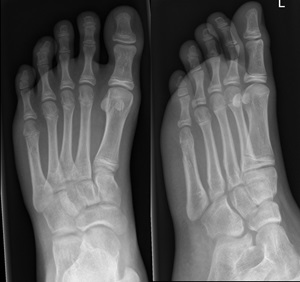

Metatarsal fractures

Undisplaced metatarsal fractures

Minimally displaced oblique of the 5th metatarsal

Fractures of distal 2nd-4th metatarsals

- CAM boot weight bearing as tolerated with Fracture Clinic follow up in 1 week.1